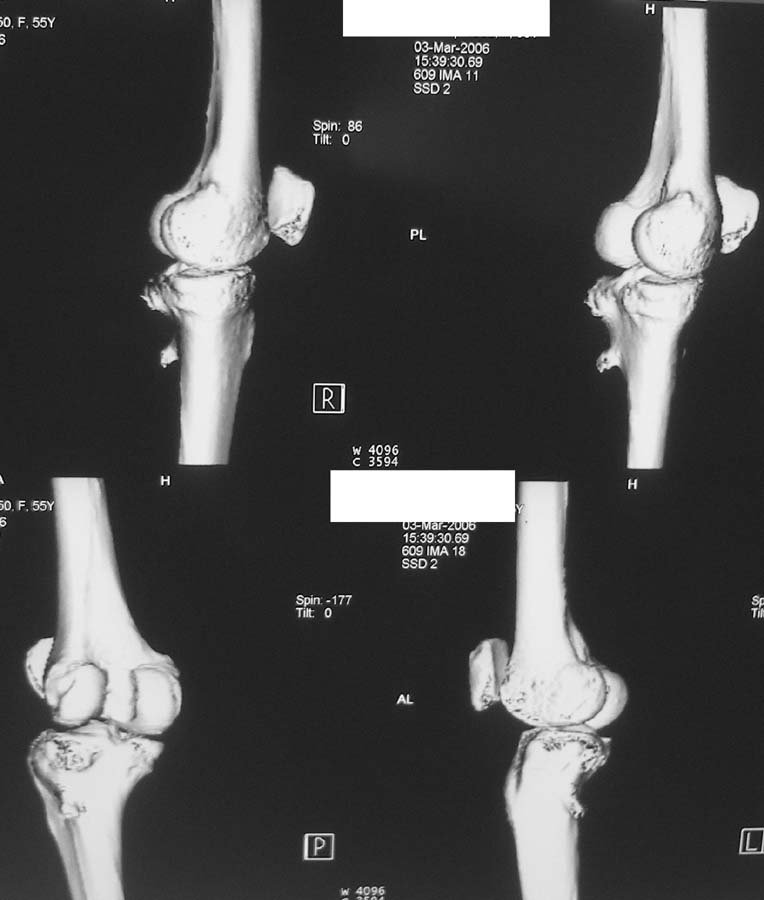

Женщина, 55 лет. С 2002 года - гонартроз. В настоящее время - боли в коленном суставе, стартовые боли, иногда в ночное время (проходит <от перемены положения ноги>).

Принимает НПВС, артрон-комплекс, внутрисуставно гиалган. Ревмопробы отрицательные. На рентгенограмме отметили сужение шейки малоберцовой кости, на спиральной КТ - экзостоз? Ваше мнение о целесообразности операции (велика вероятность повреждения нервов), предварительной биопсии?Спасибо! С уважением, А.В.Владзимирский Донецкий НИИ травматологии и ортопедии Донецк, Украина

Если боли связаны с гонартрозом, то показано тотальное эндопротезирование коленного сустава. Тип эндопротеза - мыщелковый, с сохранением задней крестовидной связки, сейчас таких моделей много (LCS, Balansis, Genesis, Scorpio, КЭКС-01 и другие, всё зависит с какими фирмами Вы работаете). Вопрос об удалении остеохондромы спорный, с одной стороны маловероятно ожидать у женщины 55 лет быстрого перерождения во вторичную хондросаркому при такой рентгенологической картине. Можно спротезировать коленный сустав и проводить рентгенконтроль каждые 6-12 мес. С другой стороны, если спротезировать и оставить остеохондрому, а она начнёт интенсивно рости, то её последующее радикальное удаление может ослабить тибиальный компонент эндопротеза. Проявляя онкологическую настороженность, остеохондрому лучше удалить первым этапом, до эндопротезирования с интервалом между операциями 6 мес. Производить биопсию в данном случае однозначно не целесообразно, так как при перерождении остеохондромы во вторичную хондросаркому на начальных стадиях малигнизации трудно гистологически отличить "добро" от "зла", и в этих ситуациях приоритет отдаётся рентгенологическим признакам. Техника операций при подобной остеохондроме стандартная - краевая резекция. Опасность повреждения малоберцового нерва существует всегда, но она зависит от мастерства хирурга и наличия микрохирургической техники (микроскоп не обязателен :)).

Вокруг коленного сустава беcсимптомные экзостозы встречаются очень часто, но они больше с медиальной стороны бедра и большеберцовой кости, и они выявляются при случайных рентгенологических исследованиях. Если нет сиптомов давления на малоберцовой нерв, то нет смысла из трогать, удаляется тогда, когда идет рост, поэтому только

наблюдение.

Насчет протезирования коленного сустава - при таком сохранном суставе навряд ли можно согласиться и совершенно согласен с Яковом, что надо искать источника боли сканированием или магнеторезонансными исследованиями.

Действительно, надо бы определиться в причине болевого синдрома. Подобные остеомы, как правило, немые. Болевой синдром может быть связан с околосуставнойт патолоией (например, поражение "гусиной лапки") или внутрисуставной. По R - граммам сустав очень даже сохранный (протезировать его явно нет необходимости), а отвергнуть внутрисуставную патологию или сразу ее максимально устранить поможет артроскопическое вмешательство. Повреждения менисков частенько симулируют остеоартроз.

Суставная щель на вид очень даже приличная. Мне кажется у больной есть варусная деформация колена, и возмможно с этим связано дегенаративное поражение медиального мениска и вся клиническая картина. Если это так, то эндопртезирование это слишком! Может что полегче: артроскопия и медиальная плюс-остеотомия.

Экзостоз скорее всего случайная находка, но динамического наблюдения безусловно требует.